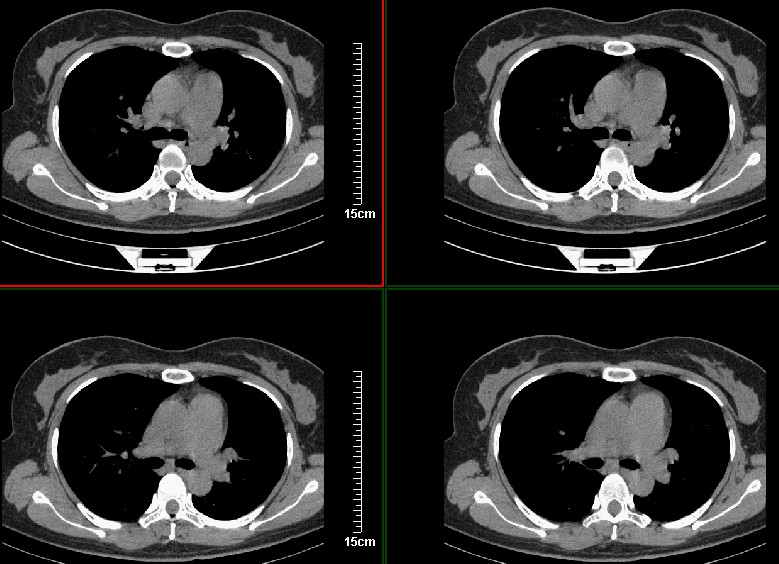

一周之后 复查结果 5mm扫描 40多岁 我们医院的护士

考虑左肺上叶周围型肺癌可能性大.

左上肺周围型肺癌可能性大,

左上肺周围型肺癌可能性大,不排除单纯感染性病变.

首先考虑左上肺周围型肺癌可能性大,但肺内炎症(肺脓肿形成前期)有待排除

左肺上叶肿块,肺窗周围有“晕征”,纵隔窗有毛刺,临床资料???只能考虑占位???